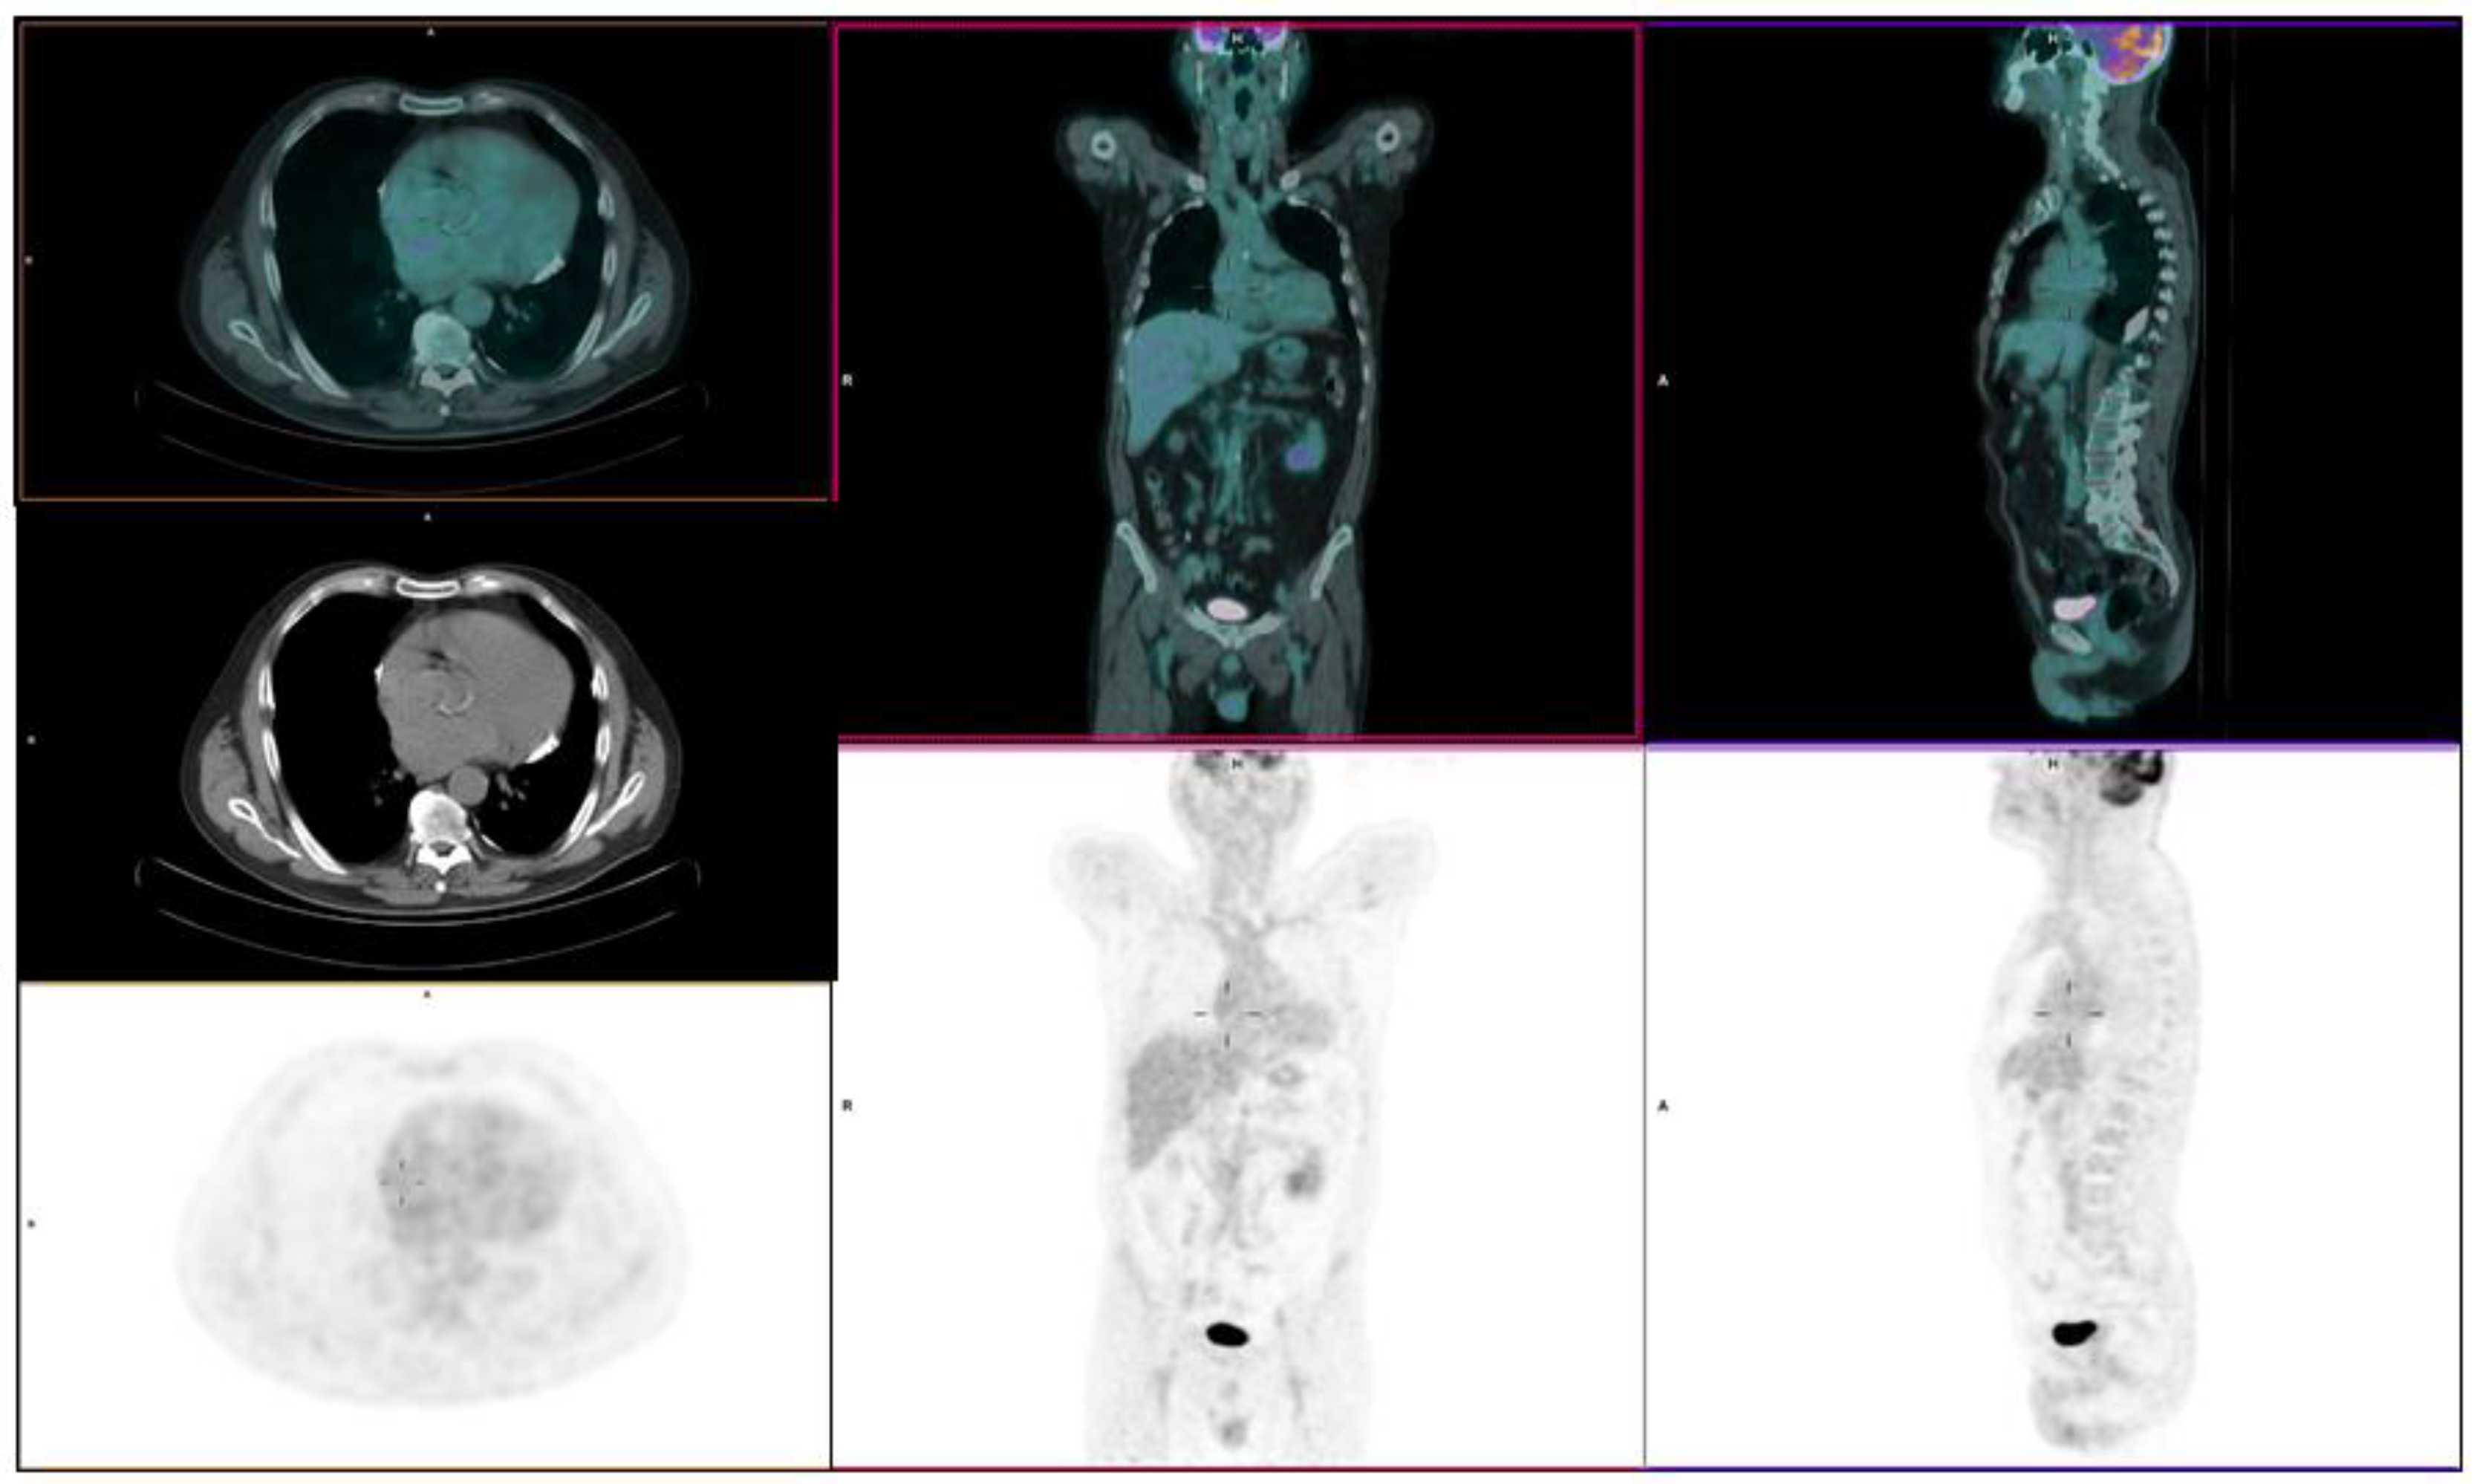

Right Atrium Mass Assessed with 18F-FDG PET/CT Scan Turns Out to Be an Uncommon Relapse of Testicular Diffuse Large B-cell Lymphoma: A Case Report

Panareo, S.; Urso, L.; Santi, I.; Rigolin, G.M.; Cuneo, A.; Cittanti, C.; Bartolomei, M. Right Atrium Mass Assessed with 18F-FDG PET/CT Scan Turns Out to Be an Uncommon Relapse of Testicular Diffuse Large B-cell Lymphoma: A Case Report. Diagnostics 2020, 10, 987. https://doi.org/10.3390/diagnostics10110987